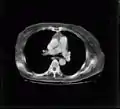

Tomografía computarizada (TAC o TC): (Artículo principal: Tomografía axial computarizada): una exploración CT, también conocida como una exploración TAC (tomografía axial computarizada), es una técnica digital que produce una imagen 2D de las estructuras de una sección delgada transversal del cuerpo. Utiliza rayos X. Los aparatos más modernos utilizan la técnica de TC helicoidal, en la que la mesa con el paciente se va desplazando al mismo tiempo que se realiza la imagen: de este modo la exploración se realiza más rápido y son posibles las reconstrucciones multiplanares y tridimensionales. Tiene una dosis de radiación ionizante mayor que la radiografía de proyección, lo cual hace que las exploraciones repetidas deban ser limitadas.

El TAC mejora el contraste de la radiología convencional, tal y como se ve en las siguientes imágenes.

La tomografía computarizada (TC), denominada en sus comienzos como TAC (Tomografía Axial Computarizada), es una técnica de imágenes digitales que ha tenido un gran impacto en el desarrollo de la medicina actual. Se basa en el uso de un haz de rayos X muy colimado, donde la radiación trasmitida a través de un objeto —en medicina, el paciente recostado en una mesa radiológica— es medida por un conjunto de detectores ubicados en oposición a la fuente de rayos X. Luego de múltiples mediciones realizadas alrededor del objeto, la respuesta eléctrica del set de detectores es enviada a un ordenador, el que mediante algoritmos computacionales (como por ejemplo, el algoritmo de retroproyección filtrada), es capaz de construir una imagen seccional del objeto utilizando la data medida y desplegarla finalmente sobre un monitor.

Esta imagen obtenida en TC es capaz de evidenciar las diferencias en las características de atenuación de las estructuras contenidas al interior de los objetos estudiados. Estas estructuras son visualizadas en el monitor con base en tonalidades de grises, las que se relacionan con un valor numérico denominado Unidad Hounsfield, asignado a cada pixel de la imagen. Este valor es calculado a partir del coeficiente de atenuación de cada material contenido en el objeto, comparado con el coeficiente del agua, usado como material de referencia. Esto mejora enormemente la resolución de contraste de la TC en comparación con la radiografía simple y la tomografía lineal. Además, mediante filtros de convolución aplicados durante el proceso de construcción de la imagen, se puede mejorar, por ejemplo, la definición de los bordes de las estructuras o reducir la presencia de ruido en las imágenes. El posterior manejo de ancho y nivel de ventana permite manipular el despliegue final de las imágenes para poner énfasis en las estructuras que se quiere visualizar de acuerdo al diagnóstico que se busca.

Imagen de corte de tomografía computarizada de pulmones con procesamiento para realce de bordes.

Imagen de corte de tomografía computarizada de ambos pulmones sin procesamiento.